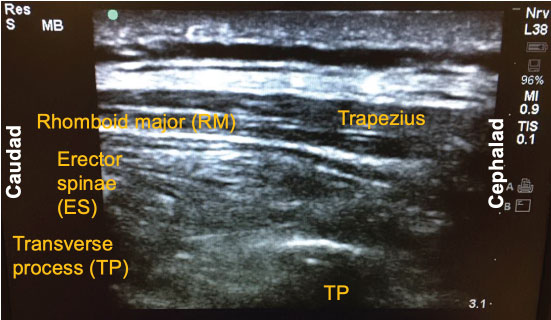

Since its introduction a few years ago, there have been numerous descriptions published on how to perform the ESP block. The following is a brief summary of the technique used to perform the block on our previously-described patient. With the patient in the sitting position, a high-frequency linear ultrasound probe was placed longitudinally on the patient's back approximately 3 cm lateral to the 5th thoracic (T5) spinous process. Three muscles above the hyperechoic transverse process were identified: trapezius, rhomboid major, and erector spinae in order of superficial to deep layers (Figure 1). A 10-cm 18-gauge Tuohy needle was inserted in-plane with the ultrasound beam at a 30° angle in a cephalad to caudal fashion. The tip of the needle was directed to the myofascial plane between the erector spinae muscle and the T5 transverse process (Figure 2). Following negative aspiration of blood, 20 mL of 0.25% ropivacaine was incrementally injected. Linear fluid spread deep to the erector spinae muscle was visualized in real-time. Finally, for continuous postoperative infusion, a 20-gauge catheter was threaded through the Tuohy needle and secured at the skin with a goal of having 5 cm of catheter left in the myofascial plane.

Figure 2: Local injection into the erector spinae (ES) plane. The tip of the needle (red circle) was directed to the myofascial plane between the erector spinae muscle and the T5 transverse process (TP). RM: Rhomboid Major.